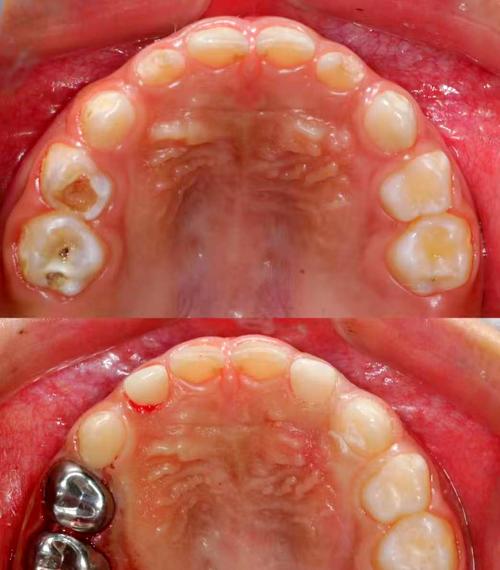

美容冠主要针对牙齿形态、色泽或轻微排列异常的改善,通过将牙齿磨小后制作全瓷冠或烤瓷冠,覆盖于原牙表面,快速实现“美牙”效果,其核心优势是治疗周期短(通常7-14天),能同时解决牙齿颜色、形状、大小等问题,尤其适用于牙齿过小、牙缝过大、氟斑牙、四环素牙等,根据材质不同,美容冠可分为全瓷冠(如氧化锆、e.max,生物相容性好、色泽自然,价格约3000元-8000元/颗)和烤瓷冠(内层金属+外层瓷,价格较低约1500元-4000元/颗,但可能存在金属过敏或牙龈黑线风险)。

部分成人患者可能需要矫正与美容冠联合治疗,牙齿严重拥挤且存在氟斑牙者,可先通过矫正排齐牙齿,再对个别牙齿进行美容冠修复,既改善排列又提升色泽;或矫正后牙齿形态仍不理想(如牙冠过短),通过美容冠调整外形,联合治疗需严格评估牙周状况,确保矫正期间牙周健康,避免因牙体磨除过多影响牙齿寿命。